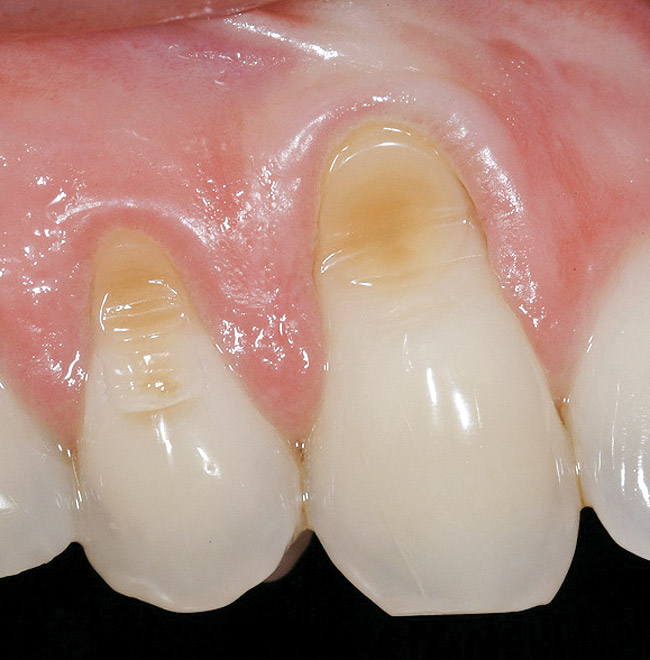

A 27-year-old non-smoking man presented for esthetic enhancement of the left central incisor, which had a pre-existing full-coverage restoration that required replacement (Figure 16). The patient had begun orthodontic treatment in the mandibular arch to correct a minor occlusal imbalance and required coronal repositioning and soft tissue grafting to correct gingival recession at the facial of the right canine, in addition to correction of the free gingival margin at the facial of the left central incisor, which was asymmetrical to the free gingival margin of tooth No. 8. Additionally, the facial gingival tissues were of a thin biotype, which at the facial surface of the left central incisor allowed for the darkened root surface to be visible through the tissue (Figure 16).

The treatment plan was to accomplish an increased zone of keratinized tissue at tooth No. 6, and increase the thickness of the facial tissue at tooth No. 9, in addition to coronally repositioning the free gingival margin. Complicating this treatment plan was the fact that at the facial surface of tooth No. 9, a biologic width invasion was present due to the prepared margin for the pre-existing restoration being placed too close to the facial alveolar crest of bone (the patient had presented to the periodontist with a provisional restoration in place). Any correction to the area would require movement of the facial margin of the tooth in a coronal fashion to re-establish the appropriate distance from the facial height of bone to the margin of the restoration. Additionally, options were given to the patient for harvesting the soft tissue, using connective tissue from the palate, or the use of an acellular dermal matrix graft, which would nullify harvesting tissue from the palate region.

Figure 16  Case Two Preoperative clinical view, maxillary left central incisor.

Figure 16